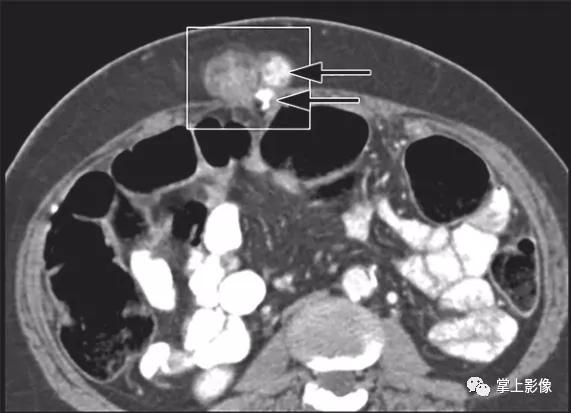

60岁女性转移性卵巢浆液性腺癌。轴位CT显示卵巢浆液性癌淋巴结转移(正方形轮廓)。注意钙化(箭头),它类似于此患者其他部位的转移性疾病(未显示)